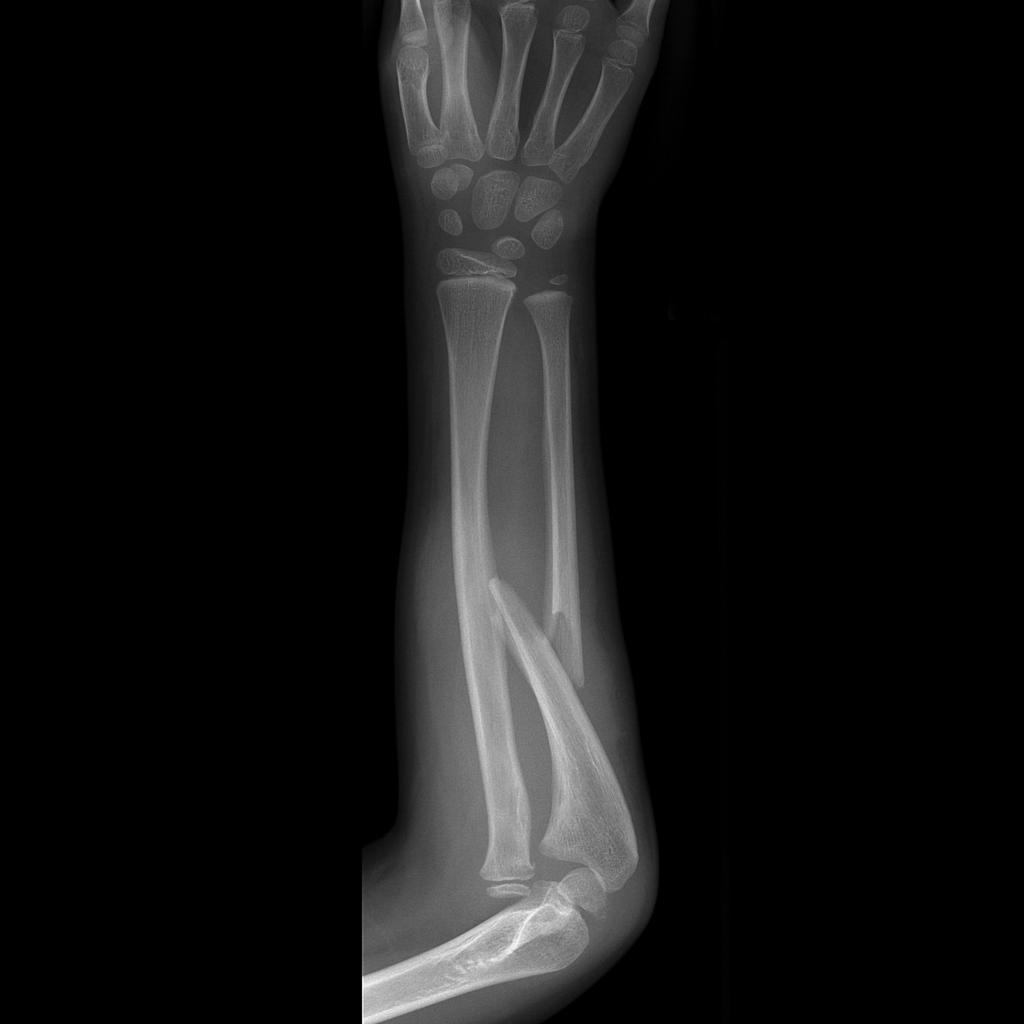

• Monteggia fracture dislocation

• Fracture of ulnar shaft with radial head dislocation

• Note radiocapitellar line